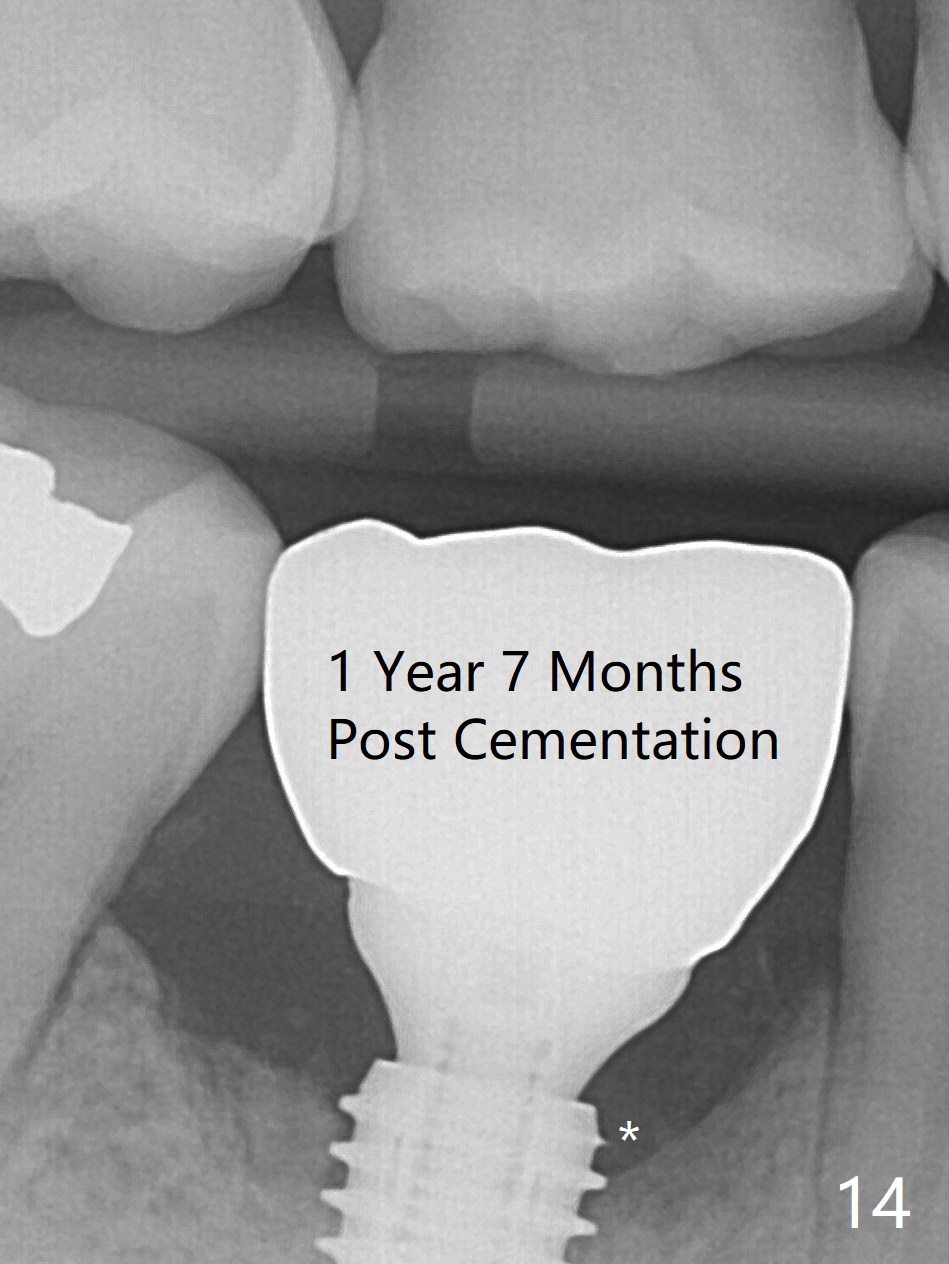

Preop oral Amoxicillin seems to be associated with reduction in the buccal and lingual (Fig.3 arrow) fistulae at #30, but there is mesiobuccal swelling (Fig.1 *) with 7 mm pocket (Fig.2). Osteotomy is initiated in the middle of the septum (Fig.3-5 S). As the osteotomy increases, it shifts mesially (Fig.6 arrow). Guided surgery is able to reduce shifting. A 5x13 mm implant is not seated completely (Fig.7) apparently due to osteotomy shifting. After removal of the bone from the osteotomy distally, the implant remains unseated with lower torque value (Fig.8). Following reuse of the 4.3 mm drill deeper by 1-2 mm, the implant is seated to a satisfactory depth (Fig.9 with increase in torque to 50 Ncm) with placement of Vera Graft (*) and a 7.5x4(3) mm abutment. After a second round of allograft placement (Fig.10 *), the implant is found to be 4 mm from the IAC. At the later stage of osteotomy, the coronal end of the septum is destroyed with loss of osteotomy depth landmark. It is apparent that the soft tissue landmark may be more reliable. The implant threads appear to be covered by the bone graft 3.5 months postop (Fig.11). The abutment is changed to 6.5x5(3) mm one before impression with minor margin prep. The bone density seems to increase 5 months postop, i.e., immediately post cementation (Fig.12) and 10 months postop (5 months post cementation (after retightening abutment), Fig.13 (*)). Periimplantitis develops mesiobuccally, consistent with bone loss 1 year 7 months post cementation (Fig.14 *); the implant seems to have been buccally placed. Bone graft is necessary with PRF or GEM21S if the vein is small and 6-month membrane with a hole around a 7.5x4(4) cemented abutment for easy wound closure. Take 5x5 CM CBCT to determine which wall has defect, buccal or lingual. Check mesial contact. If so, remove the crown, reseat the abutment (possible incomplete seating) and re-impress after bone graft.